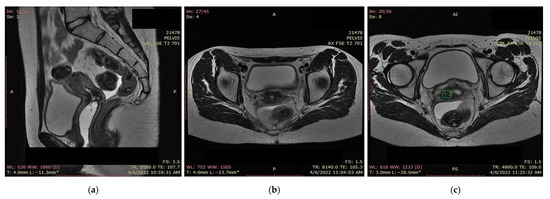

A pelvic MRI was recommended to our patient, as it would be able to provide an accurate anatomic localization of the mass and its relationship with the surrounding organs. It revealed an expansive solid cervical mass that developed between the internal and external cervical orifice, occupying the left vaginal recess, with imprecise boundaries being observed at this level. Axial and sagittal T2-weighted images showed a 53 × 78 × 46 mm mass that was hyperintense compared to normal myometrium, and axial T1-weighted images showed an isointense mass compared to the myometrium that was occupying the uterine cervix and upper vagina. The ovaries and the uterine body were normal in size, and a right external iliac adenopathy was also detected (Figure 1).

Figure 1. Pelvic sagittal T2–weighted sequence: the green highlighted area represents the circumferentially developed cervical tumor mass with intermediate T2 signal that includes both the endo- and the ectocervix protruding into the upper vagina.

Figure 13. (a) MRI and (b) CT—significant favorable post-radiotherapy and chemotherapy response, with the persistence of a necrotic and ulcerative cervical area and a possible residual lesion on the right side of the cervix (the green highlighted area).

Figure 14. (a) MRI and (b,c) CT: almost completely undetectable lesion post-radiotherapy and chemotherapy response with the persistence of an involute area of necrosis and ulceration situated at on the topography of the former tumor (the green highlighted area).